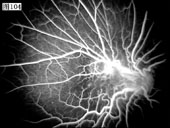

101 102 103 104